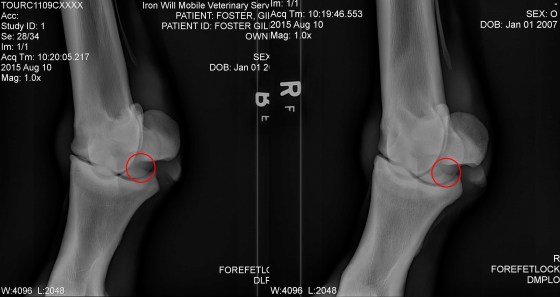

The second chip is a bit tricker to spot. It’s back by the sesamoid bones, and here we are looking through the fetlock at a diagonal angle. For a better view of what the chip looks like, here is the other side of the fetlock compared to the bone chip.

On the left you can see that the edges of the bones are nice and smooth, whereas on the right, there’s a decent sized chunk missing from the lower piece, and some jaggedness to the upper. Very scientific terms here, but you get the idea. The surgeon theorizes that the chip in this area (top left of the circle) may be buried in the surrounding soft tissue, so it is not clear until we delve into it whether or not the chip is worth removing.